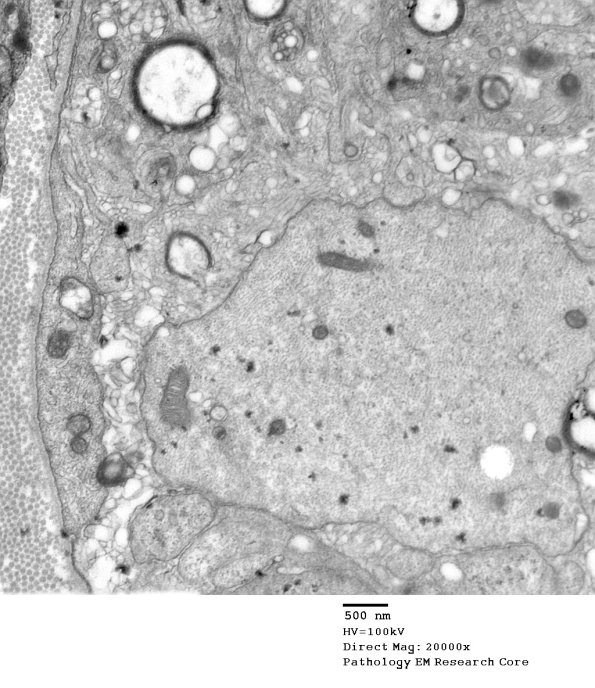

3B1A-C Multiple cells have entered the sub-basal lamina space and engulfed myelin debris, a process largely completed. (electron micrographs)